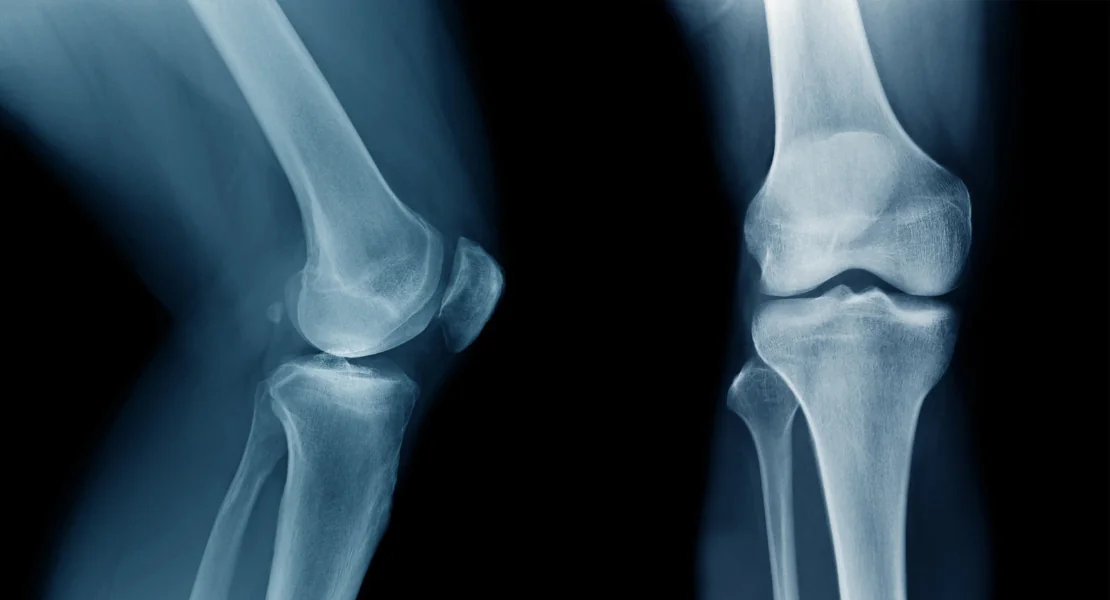

Dor no joelho em Perdizes, SP? Saiba as causas mais comuns, quando procurar um ortopedista e como é o tratamento com convênio na SUORT.

Dor, rigidez e estalos no joelho? Entenda a gonartrose, seus graus e como o tratamento conservador em Perdizes pode evitar a cirurgia.

Dor ao torcer o joelho, travamento ou inchaço? Saiba quando a lesão de menisco exige cirurgia e quando a fisioterapia resolve em Perdizes, SP.

Dor no joelho após lesão, cirurgia ou desgaste? Conheça o protocolo de fisioterapia ortopédica da SUORT em Perdizes, São Paulo, com atendimento por convênio.

A dor no joelho é uma das queixas ortopédicas mais comuns — e, na maioria dos casos, tem tratamento eficaz sem cirurgia.